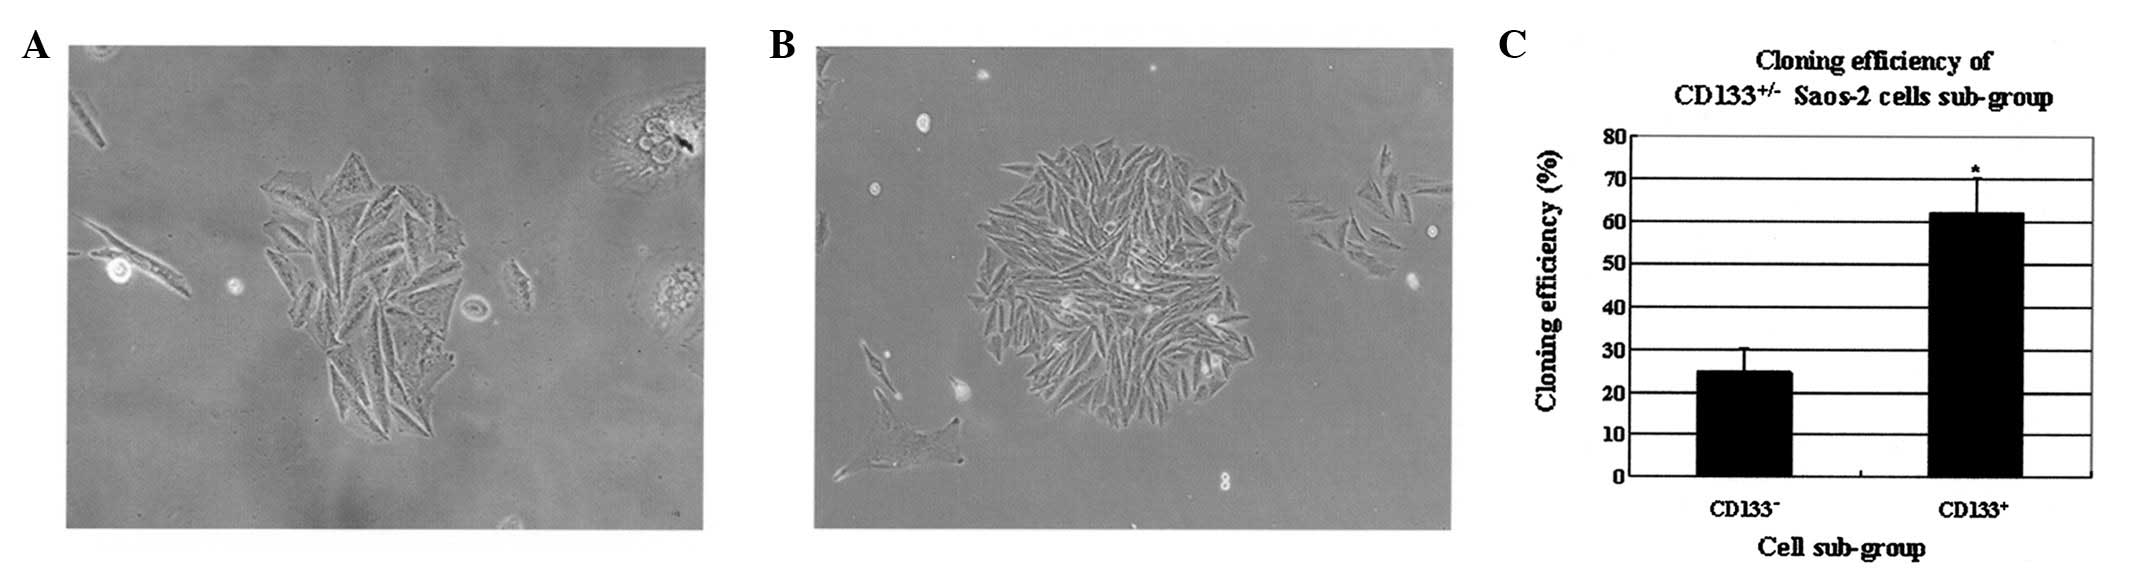

Cluster of differentiation 133 (CD133) is recognized as a stem cell marker for normal and cancerous tissues. Using cell culture and real‑time fluorescent polymerase chain reaction, CD133 expression was analyzed in osteosarcoma tissue and Saos‑2 cell lines. In addition, cancer stem cell‑related gene expression in the Saos‑2 cell line was determined to explore the mechanisms underlying tumorigenesis and high drug resistance in osteosarcoma. CD133+ cells were found to be widely distributed in various types of osteosarcoma tissue. Following cell culture, cells entered the G2/M and S cell cycle stages from G0/G1. Levels of CD133+ cells decreased to normal levels rapidly over the course of cell culture. Colony forming efficiency was higher in the CD133+ compared with the CD133‑ subpopulation of Saos‑2 cells. Expression levels of stem cell‑related genes, including multidrug resistance protein 1 (MDR1) and sex determining region Y‑box 2 (Sox2) in the CD133+ subpopulation of cells were found to be significantly higher compared with the CD133‑ subpopulation. These observations indicate that CD133+ Saos‑2 cells exhibit stem cell characteristics, including low abundance, quiescence and a high potential to undergo differentiation, as well as expression of key stem cell regulatory and drug resistance genes, which may cause osteosarcoma and high drug resistance.